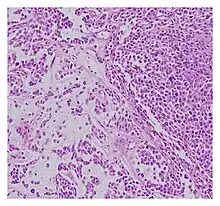

| Histopathological examination of malignant chondroid syringoma | |

Histologically, these malignant mixed tumours have epithelial and mesenchymal components and are very large, nodular, circumscribed, and nonulcerated.[11] They are morphologically identical to pleomorphic adenoma and have a female predilection.[4] They range from developing deep dermal to subcutaneous nodules and metastasise at a very high rate.[4][8] Malignant mixed tumours can emerge "de nova or more rarely develop from a cartilaginous syringoma."(IADVL, 2004)[11]